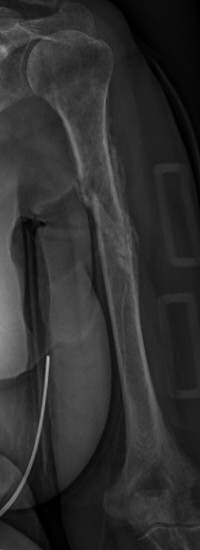

Exempel på humerusfraktur som behandlats icke-kirurgiskt, röntgenbilder efter 19, 40 resp. 71 dagar